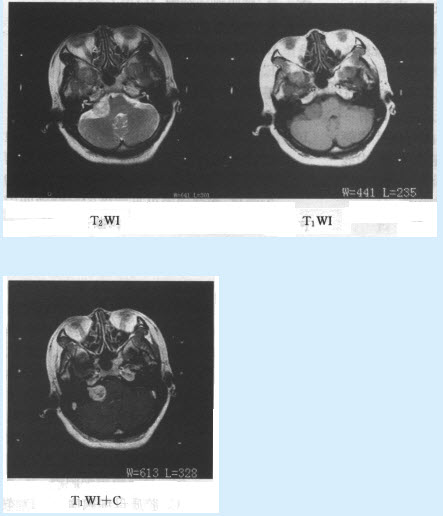

患者,男性,79岁,上腹部疼痛,不易缓解,吐咖啡色血液。行上腹部CT增强扫描,如下图